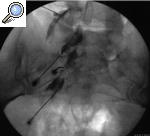

La técnica se realiza en quirófano, con monitorización estándar. El paciente se coloca en decúbito supino. Para bloquear la rama articular del nervio obturador (fig. 4) la aguja debe situarse en el aspecto anteromedial de la porción extraarticular de la articulación de la cadera, medial a la arteria femoral y bajo el ligamento inguinal. La punta se dirige a la unión del isquion con el pubis8.

Figura 4. Bloqueo de cadera. 1: intraarticular; 2: nervio femoral; 3: nervio obturador.

En el caso de la rama articular del nervio femoral (fig. 4), la aguja se sitúa bajo la espina ilíaca anteroinferior, en el aspecto anterolateral de la porción extraarticular. La punta se aloja bajo la espina ilíaca anteroinferior, cerca del margen anterolateral de la articulación de la cadera9.